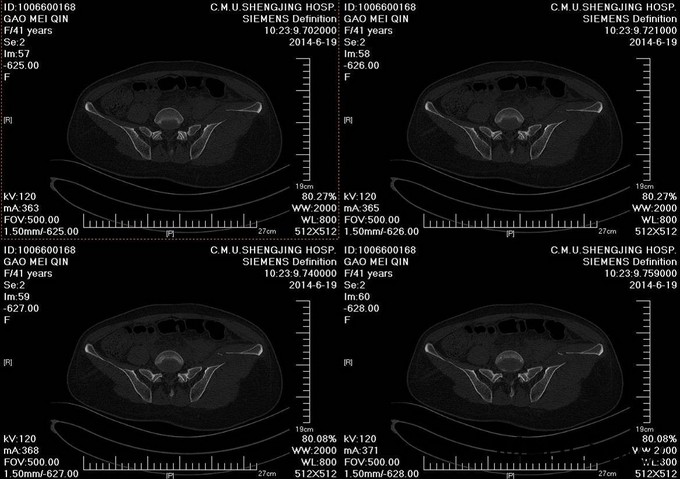

主诉:车祸外伤后左髋部疼痛伴活动受限4天 患者于2014年6月12日早6点左右被皮卡车撞伤,伤后患者出现一过性昏迷,被急诊送往当地医院,行DR及CT检查后,诊断为:左髋臼骨折,于当地医院骨科行骨牵引、抗炎补液等对症治疗后,现为求进一步治疗转入我科,患者病来无头晕头痛,无恶心呕吐,已排气排便.

患者左下肢股骨髁上骨牵引中,左髋部肿胀,臀部可见淤血瘀斑,骨盆分离挤压试验(+),左大腿肿胀,左下肢无明显短缩,纵向叩击痛(+),左下肢小腿外侧及足背麻木感,足背伸肌力正常,双足趾可活动,双侧足背动脉可触及搏动